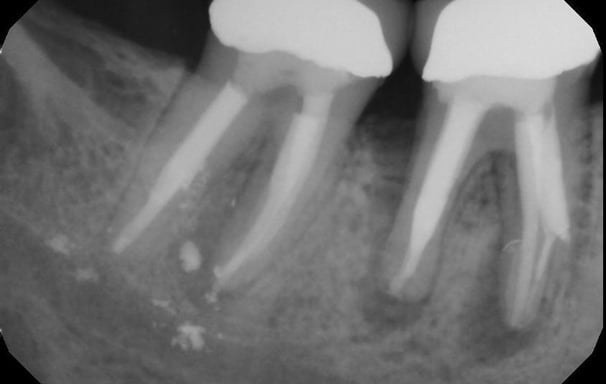

Diagnóstico de dolor dental

Consiste en identificar la causa del dolor en un diente, ya sea por caries, infecciones u otras afecciones. Se realiza mediante exámenes clínicos, radiografías y pruebas de sensibilidad.

Evaluación de la vitalidad dental

Se determina si la pulpa del diente (el tejido interno) está viva o muerta. Esto se realiza mediante pruebas de sensibilidad térmica o eléctrica para evaluar la respuesta del diente.

Se identifica si hay fracturas en la raíz del diente, que pueden causar dolor, infecciones o problemas de estabilidad dental. Se utilizan radiografías y exámenes clínicos para este diagnóstico.

Evaluación de fracturas radiculares

Se analiza el estado de dientes que han recibido tratamientos endodónticos anteriores para verificar su éxito y determinar si se necesita un retratamiento.

Evaluación de dientes con tratamientos previos